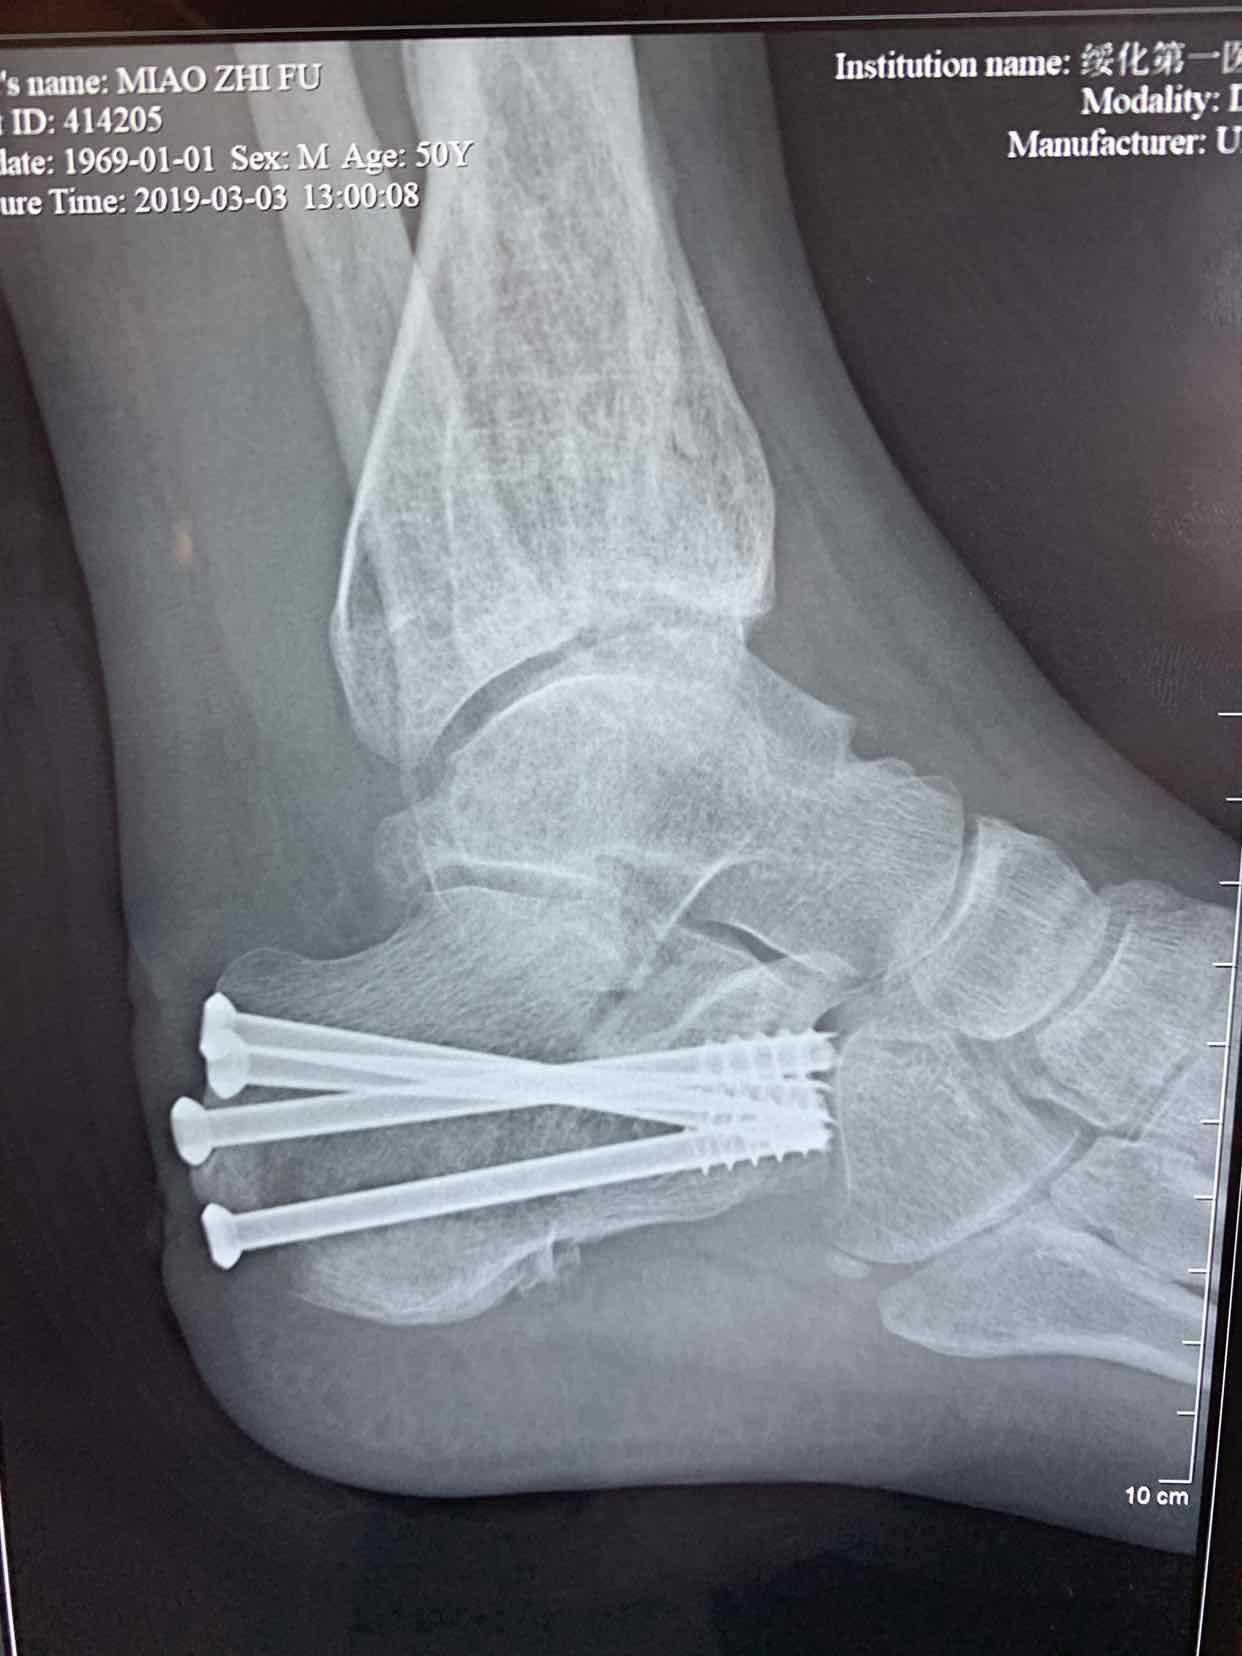

诊断为左侧跟骨粉碎性骨折。在腰麻下行闭合复位空心钉内固定术。术后恢复较好。

跟骨骨折临床常见。处理方式很多,本人还是喜欢选择微创治疗,请各位专家指正。